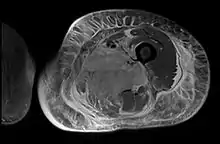

Creatine kinase may be normal or increased probably depending upon the stage of the condition when sampling is undertaken. ESR is elevated. Planar X-ray reveals soft tissue swelling and may potentially show gas within necrotic muscle, Bone scan may show non specific uptake later in the course. CT shows muscle oedema with preserved tissue planes (non-contrast enhancing). MRI is the exam of choice and shows increased signal on T2 weighted images within areas of muscle oedema. Contrast enhancement is helpful but must be weighed against the risk of Nephrogenic Systemic Fibrosis as many diabetics have underlying chronic kidney disease. Arteriography reveals large and medium vessel arteriosclerosis occasionally with dye within the area of tissue infarction. Electromyography shows non specific focal changes.